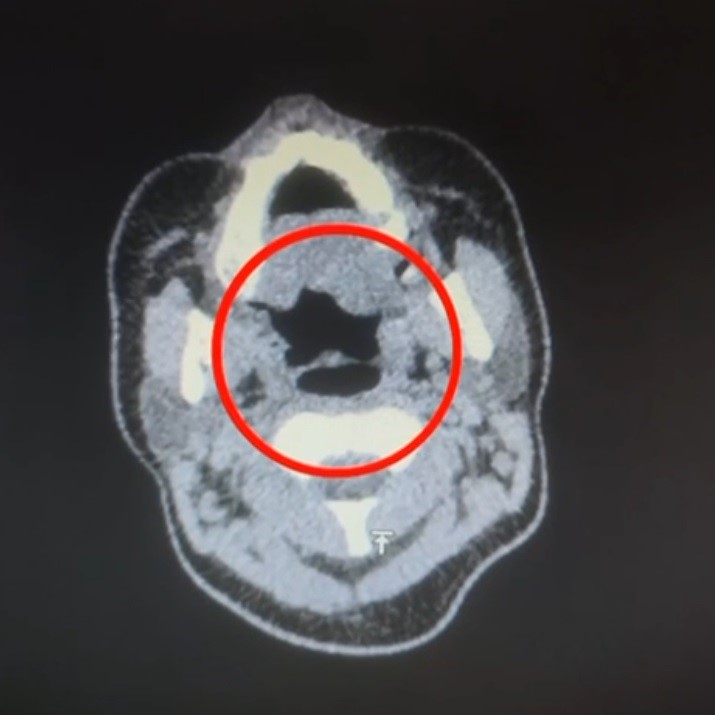

Kayseri'de uluslararası uyuşturucu madde ticareti yapan kuryenin midesinde 50 adet kapsül şeklinde 500 gram uyuşturucu madde ele geçirildi. Kayseri İl Emniyet Müdürlüğü Narkotik Suçlarla Mücadele Şube Müdürlüğü ekipleri, uluslararası uyuşturucu madde ticareti yapan kurye şahıslara yönelik operasyon düzenledi. Operasyonda A.R.'yi (27) gözaltına alan ekipler, şahsı hastane muayenesine götürdü. Şüphelinin yapılan iç beden muayenesinde, mide kısmında bulunduğu tespit edilen 50 adet kapsül şeklinde toplam 500 gram uyuşturucu madde ele geçirildi. 'Uyuşturucu madde ticareti yapmak' suçundan gözaltına alınan şüpheli emniyete götürüldü.